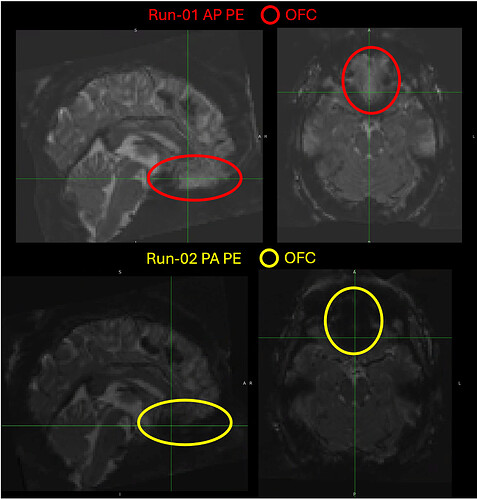

As I was checking the ROI overlays for my subjects’ BOLD data (which has been registered to MNI152NLin2009cAsym space) I noticed that the signal in the orbitofrontal cortex (OFC) on the PA-acquired image is much worse that that on the AP acquired images. Here is an example of what I mean:

This is concerning to me, because I am interested in the medial OFC (mOFC) as one of my ROIs. I am also interested in areas of the hindbrain as part of my analyses.

A qualitative inspection of the time-series information shows that the intensity values for the mOFC during PA scans is consistently lower than it is on the AP scans. Other ROIs I am interested are not effected in as consistent a manner insofar as they do not seem consistently higher or lower during one PE scan versus the other.